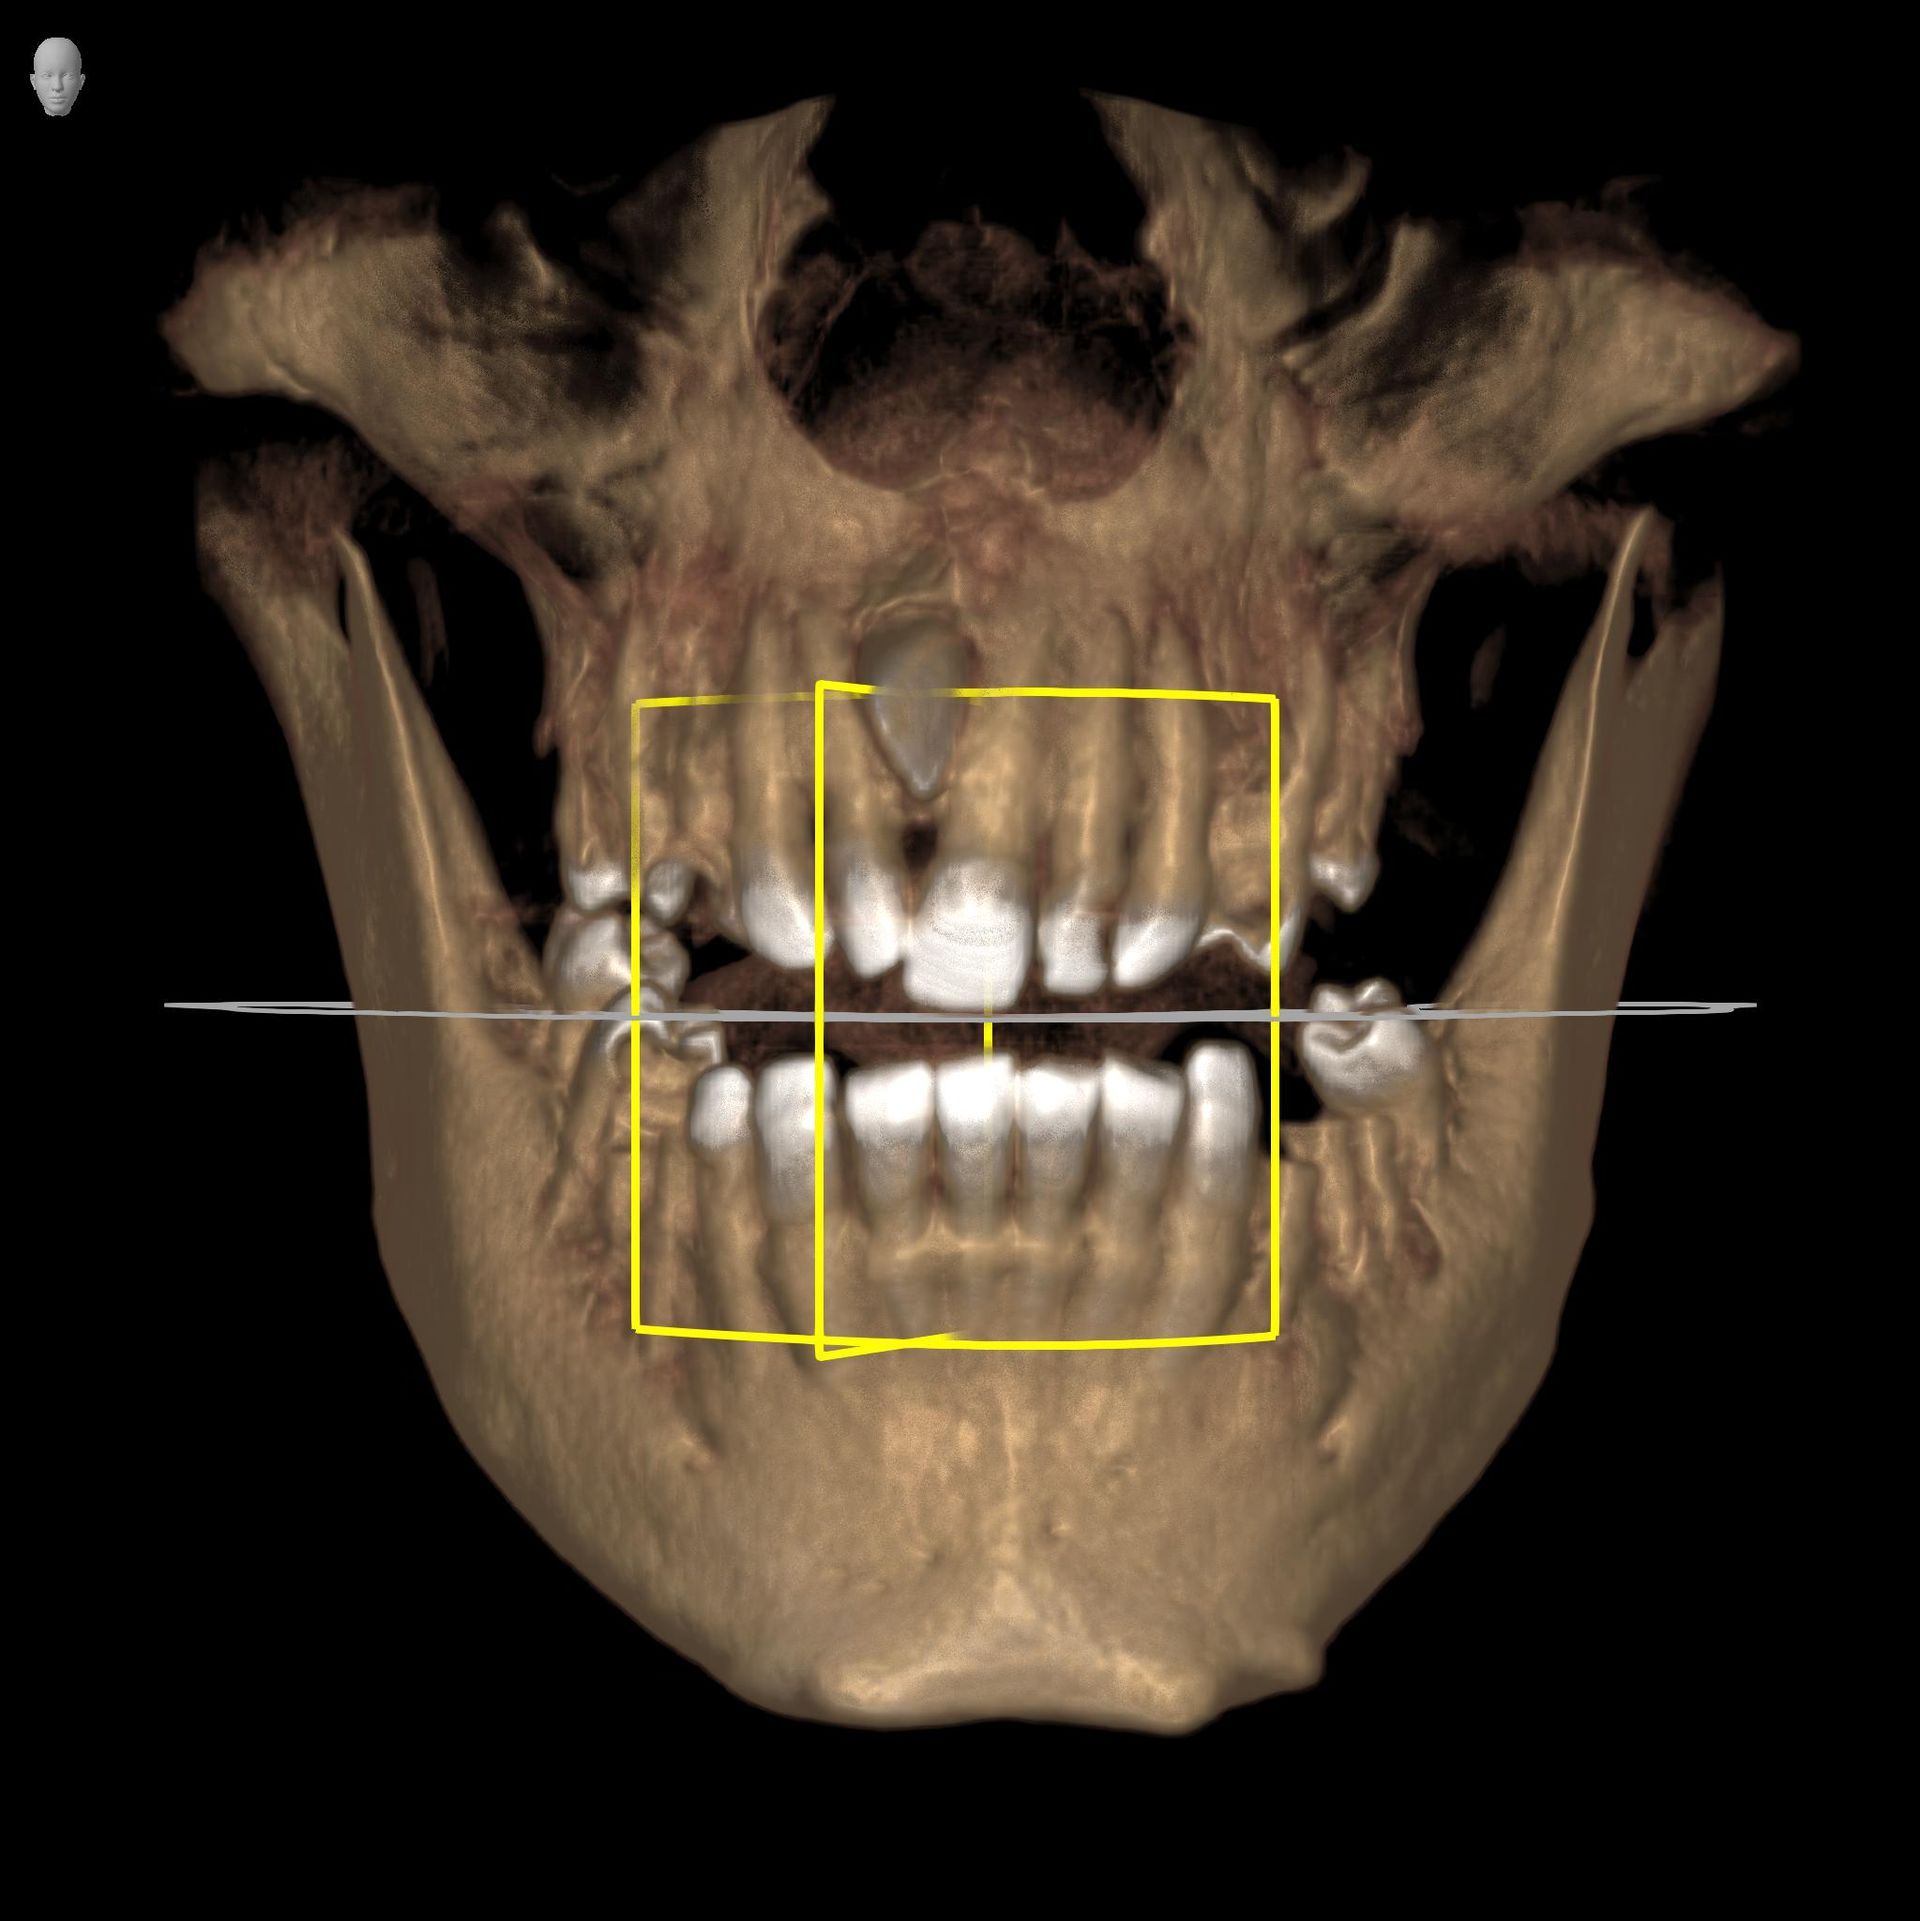

La funzione 3D, permette la visualizzazione completa delle strutture dentarie, ossee, in tre dimensioni, con ottima risoluzione di contrasto per lo studio dei tessuti molli.